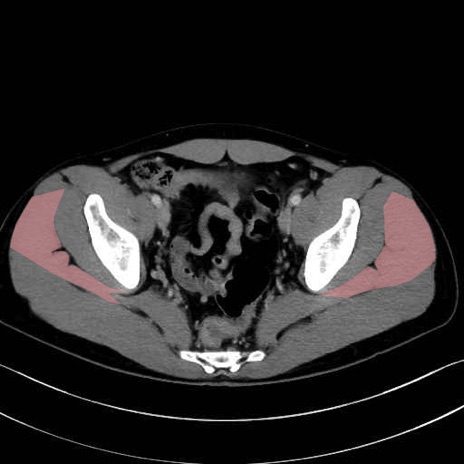

中殿筋 (Gluteus medius)